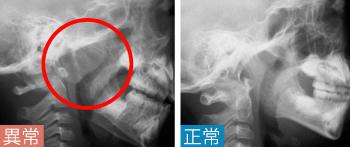

症状の例

口呼吸・いびき・鼻閉・鼻水・耳閉塞感・難聴

検査

レントゲン

検査結果の例

[レントゲン]

扁桃が大きくなり(アデノイド肥大)、気道が狭小化

病名

アデノイド増殖症

Point

• アデノイド増殖症は、幼児に多い疾患です。